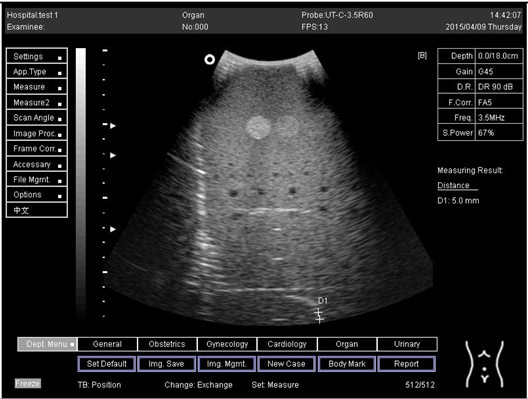

Table A5. The image taken for focal zone determination in different depth for curve probe.

Depth (cm)Diagram

14.0Biomimetics 07 00130 i031

16.0Biomimetics 07 00130 i032

18.0Biomimetics 07 00130 i033

24.0Biomimetics 07 00130 i034